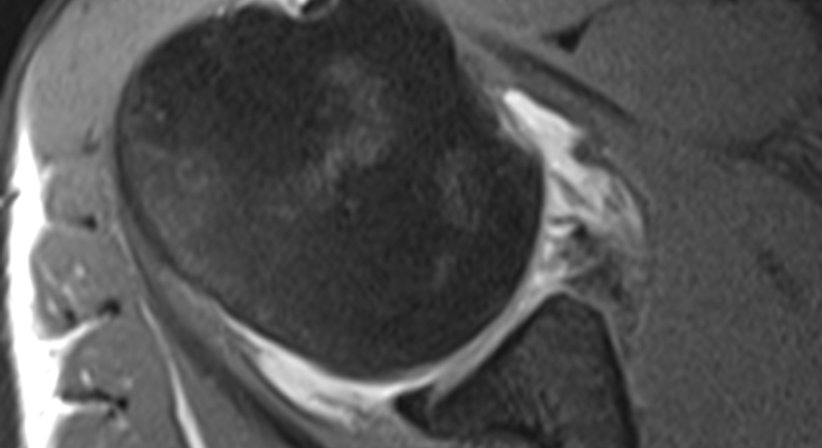

Um eine Schulterinstabilität genau diagnostizieren zu können, werden in der Regel mehrere klinische Tests (Anteriorer Translationstest, Relocation Test, Anterior Apprehension Test, Sulcus Zeichen) sowie eine Magnetresonanztomografie mit oder ohne Kontrastmittel (Arthro-MRT) durchgeführt. Mögliche Schäden an knorpeligen oder sehnigen Anteilen des Gelenks, insbesondere am knorpeligen Pfannenrand, lassen sich dadurch besser darstellen.